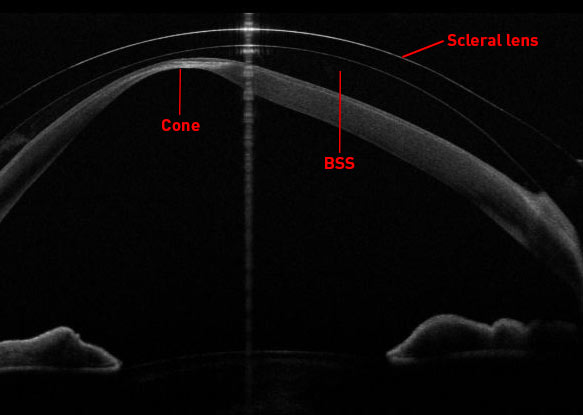

For those unfamiliar, scleral lenses are a type of contact lens that vaults over the cornea and rests on the white part of the eye (the sclera). The lens is filled with sterile BSS solution, which fills the space between the cornea and the lens. This makes scleral lenses particularly beneficial for those with irregular corneas, such as our patient with keratoconus, as the multitude of small irregularities on the surface of the cornea that cause the visual disturbances and higher order aberrations become filled with the fluid, and as a side benefit, is extremely good at treating severe dry eye too. At ELZA, our Senior Optometrist, Léonard Kollros, is a highly experienced, expert scleral lens fitter, and the case we report here is one of his.

OCT image of the cornea with a fitted scleral contact lens